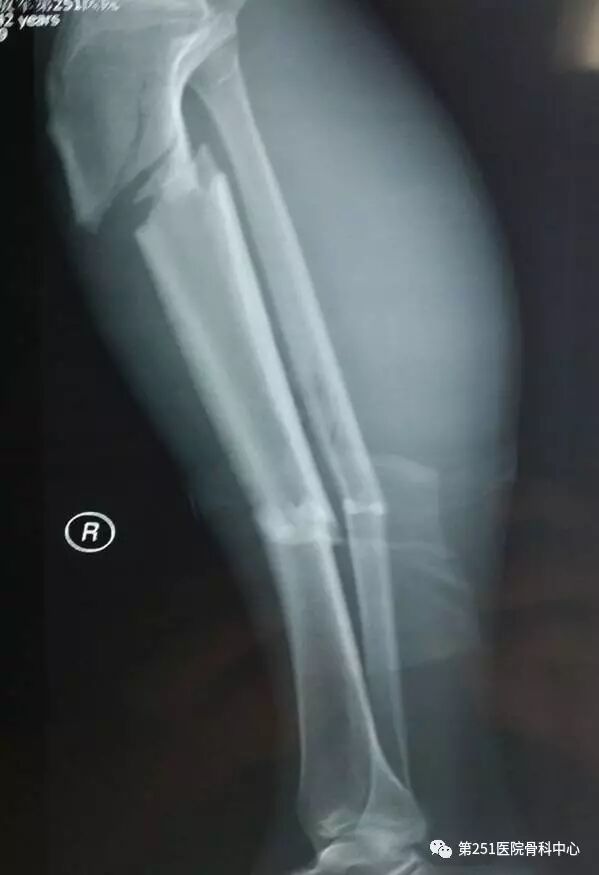

病例1:男性,40岁,车祸伤,胫腓骨多段骨折。

![]()